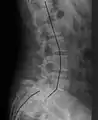

X-ray picture of a grade 1 isthmic anterolisthesis at L4-5

X-ray of a grade 4 anterolisthesis at L5-S1 with spinal misalignment indicated